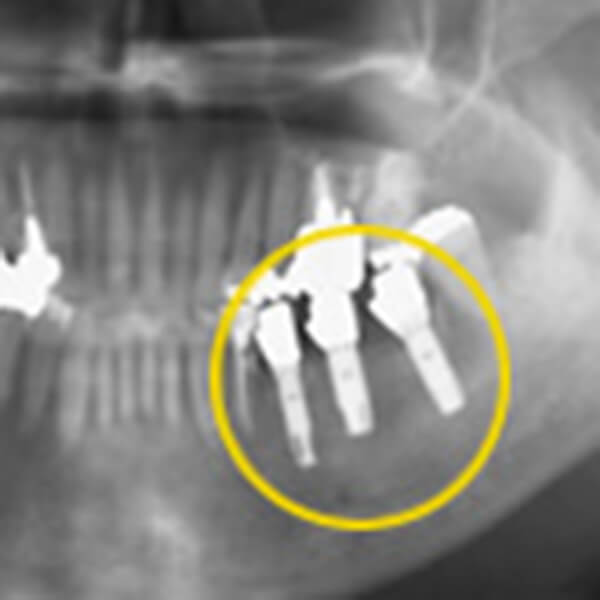

インプラント埋入後

インプラント埋入後のレントゲン写真。